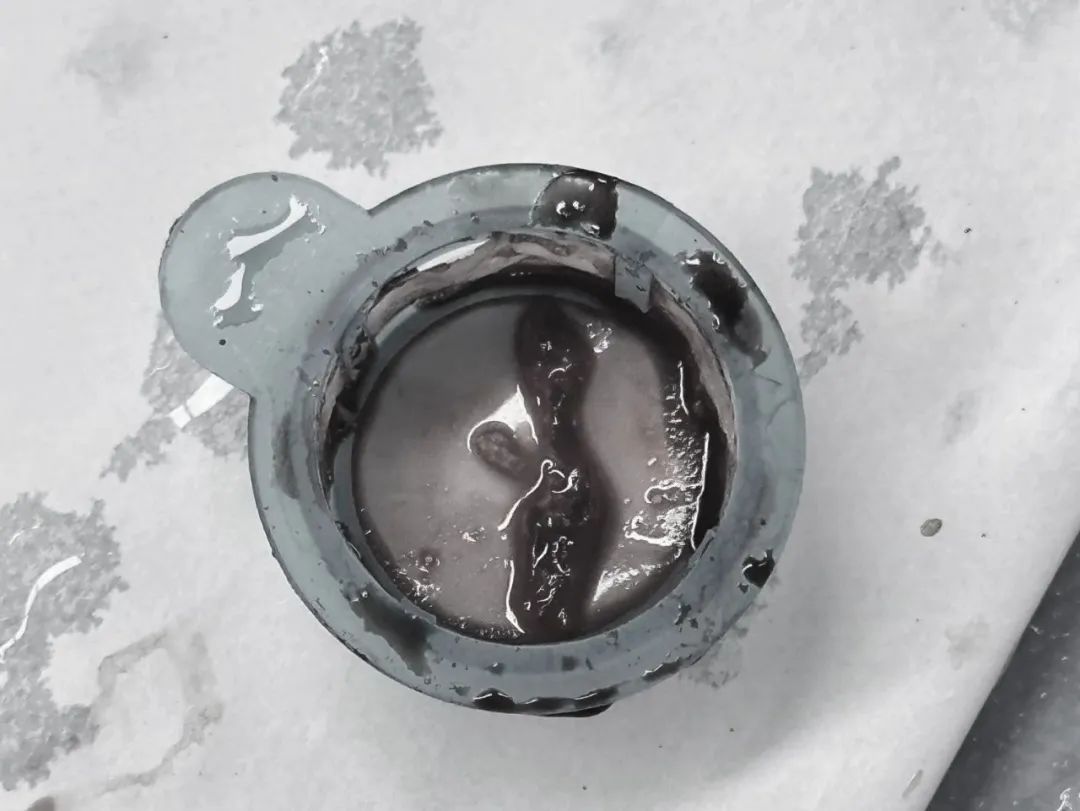

更凶险的是,就在抽吸血栓的过程中,突发紧急状况:患者心脏室速、室颤、电风暴接踵而至,医护团队连续进行 4 次电除颤、电复律。随着最后一块暗红色血栓被抽出,血流终于恢复。

抽吸出的血栓,已做褪色处理